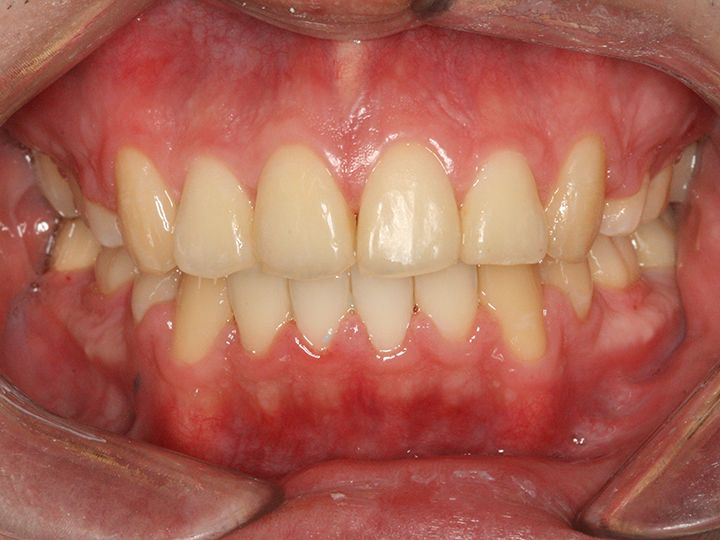

「ライムナム歯科病院」はラミネートやセラミックを使った審美治療、美白治療、インプラント、歯列矯正など、あらゆる歯の悩みに応える歯科病院です。2004年の開業以来、常に新しい技術と診療機器を取り入れ、韓国内外の患者の信頼を集めてきました。特に忙しい現代人の悩みである時間短縮治療メニューが充実。来院当日にできるだけ解決できるようなシステムを構築しています。独自の歯科技工所を持っているのもその理由のひとつ。また20年にわたるノウハウの蓄積を生かし、患者の負担を減らせるように痛みを減らす施術にも力を入れています。